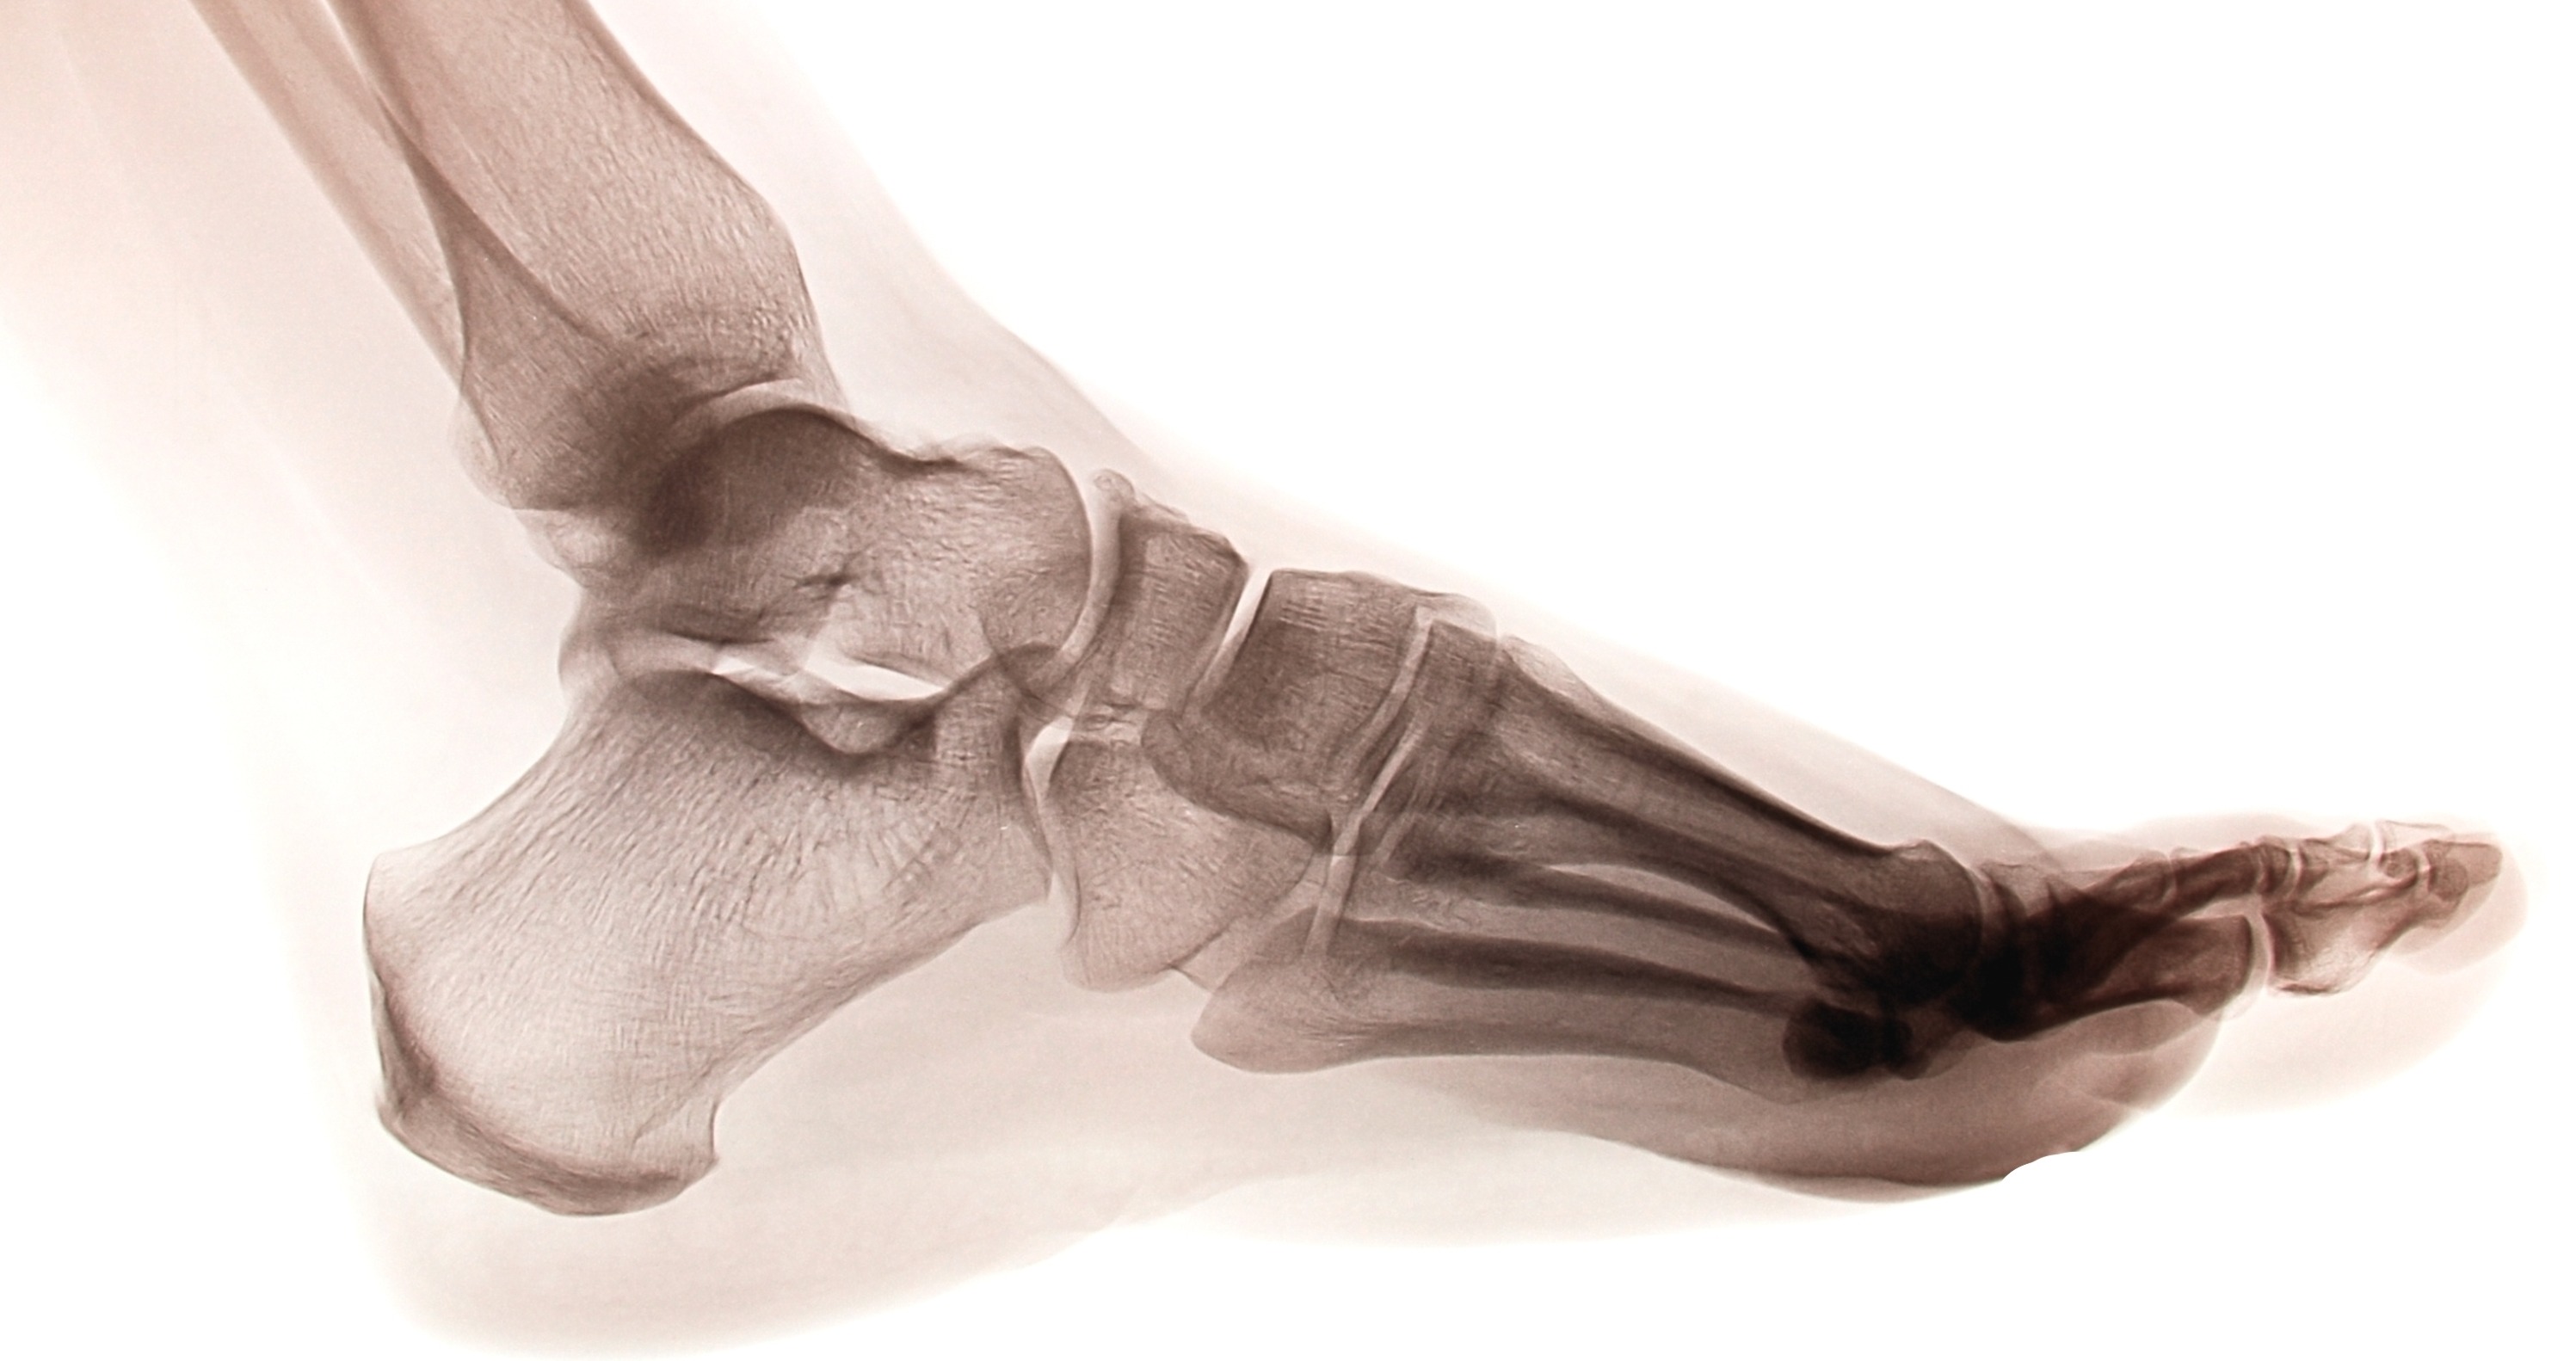

The Anatomy Behind Foot and Ankle Biomechanics

To comprehend the biomechanics of the foot and ankle, you must first understand the intricate structure that enables movement. The foot is divided into three main anatomical regions: the hindfoot, midfoot, and forefoot—each playing a unique role in foot biomechanics.

Hindfoot Biomechanics

The hindfoot, located immediately under the ankle joint, forms the posterior foundation of foot biomechanics. This region consists primarily of two crucial tarsal bones:

• Talus: The primary bone connecting the foot to the lower leg

• Calcaneus: The heel bone that bears initial ground contact forces

The hindfoot's biomechanical function centers around the subtalar joint, which allows for inversion and eversion movements crucial for adapting to uneven surfaces and absorbing impact forces.

Midfoot Biomechanics

The midfoot contains five additional tarsal bones that contribute significantly to the biomechanics of the foot:

• Navicular bone

• Cuboid bone

• Three cuneiform bones (medial, intermediate, and lateral)

The junction between the midfoot and hindfoot, known as Chopart's joint, plays a vital role in foot biomechanics by allowing the foot to adapt its shape during different phases of gait.

Forefoot Biomechanics

The forefoot includes the metatarsals, phalanges, and sesamoid bones. The Lisfranc joint, where the midfoot and forefoot meet, is crucial for push-off mechanics during the propulsive phase of gait.

The complete foot structure encompasses:

• 28 bones working in coordination

• 112 ligaments providing stability

• 33 joints enabling complex movement patterns

• 34 muscles generating and controlling motion

This intricate network demonstrates why foot and ankle biomechanics are so complex and why small dysfunctions can have significant impacts on overall movement quality.

The main players in the biomechanics of the foot and ankle are the tibiotalar joint and the transverse tarsal joint. The tibiotalar joint, otherwise known as the ankle joint, is what allows the foot to move up and down with help from the muscles in the front and back of the leg. The transverse tarsal joint is what helps movement go forward, and aids with shock absorption and heel rise. The tendon attached to the joining helps the bone move, and when it’s not moving (i.e., absorbing shock), it locks.Biomechanics of the ankle joint anatomy